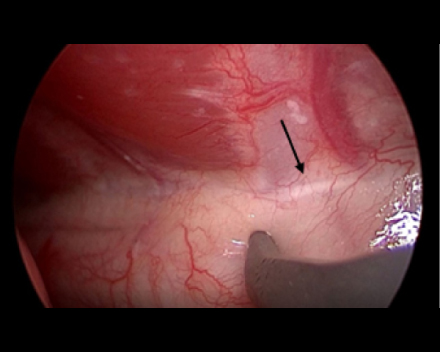

胸腔鏡で覗くと胸管がキレイに見えます(黒矢印)。

これを鉗子で丁寧に剥離していきます

反対側も同じように剥離していきます。

必ず、反対側の胸管も確認できるところまで剥離します。(黒矢印)

反対側もクリップ3-4本止めて、結紮します。

これで胸管結紮は終了です